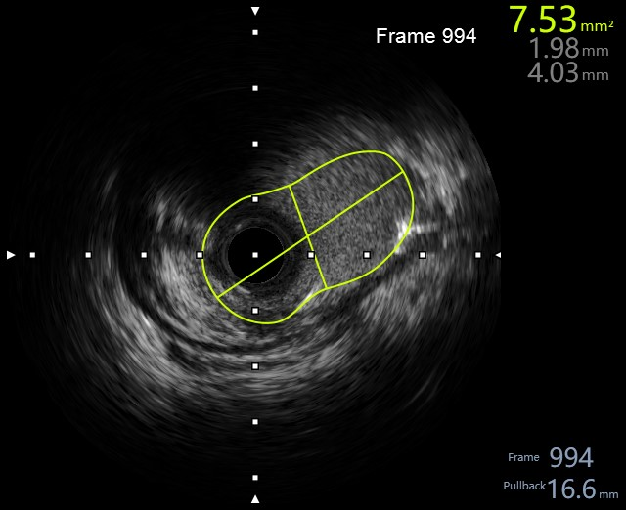

2,由远至近IVUS评估,不同切面对应不同面积,提示左主干面积4~5mm²,属于重度狭窄,需要介入治疗。

5,植入后,复查ivus,评估支架植入效果。

6,IVUS 评估后,最小面积未达到8mm²最小官腔面积。需进一步后处理。

7,给与4.0x15mm非顺应性球囊进行高压后扩张,压力维持在16~20atm。最后检查血管影像。